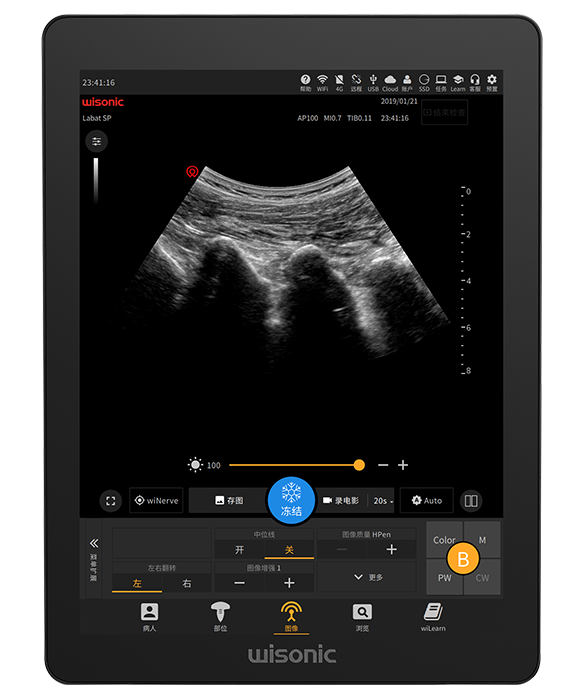

21.3

-inch Large Touch Screen Display

Anti-glare, full size, high sensitivity

Simplified Control Panel

Built-in fingerprint sensor, and smooth trackball

Full Touch Screen Display

Support Liquid Disinfection

Multi-touch Operation

Minimal Panel for Clinical Customization

High Sensitivity Waterproof Trackball

Anti-splash

Multi-function Joystick

wiNerve

AI Intelligent Nerve Recognition

Real-time Recognition

Cloud Solution

Support Multiple Nerves

Labat Probe Family

Full-range probes for versatile applications

Excellent Clinical Images

Application pictures